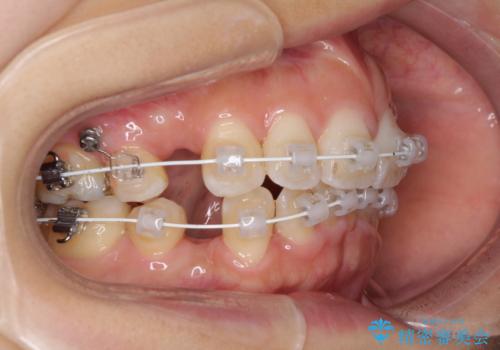

- 審美装置

- 2年5ヶ月

- 上下の出っ歯を気にして来院された患者様です。

口元を積極的に引っ込めるために、上下左右の第一小臼歯を4本抜歯することとしました。

下顎の正中を上顎に合わせる処置が難航し、期間が長引きました。

最終的には上下の正中も合い、横顔の印象が変わるほどスッキリとした口元となりました。